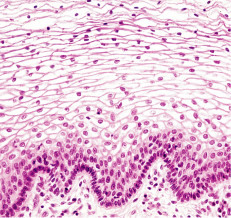

stratified squamous

consist of several layers; functions in protection